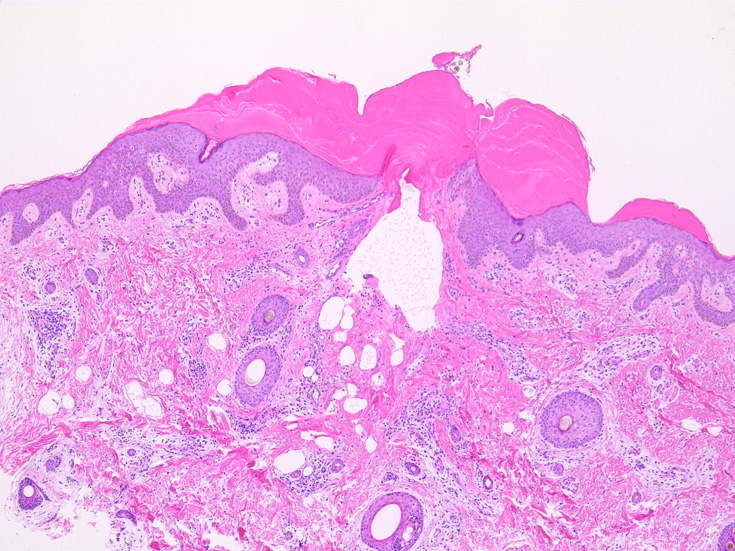

IWT-case01 66yo male. 3週間前(!)南アルプスに登山. 腹部皮膚のイボ様腫瘤に気づき来院。

マダニと思われる虫体を皮膚ごと切除した。

IWT-case02 1歳9ヶ月男児 項部の血豆様腫瘤に気づき来院.

(case02の皮膚表面にみられる硝子様の層がそれに相当するようです。)